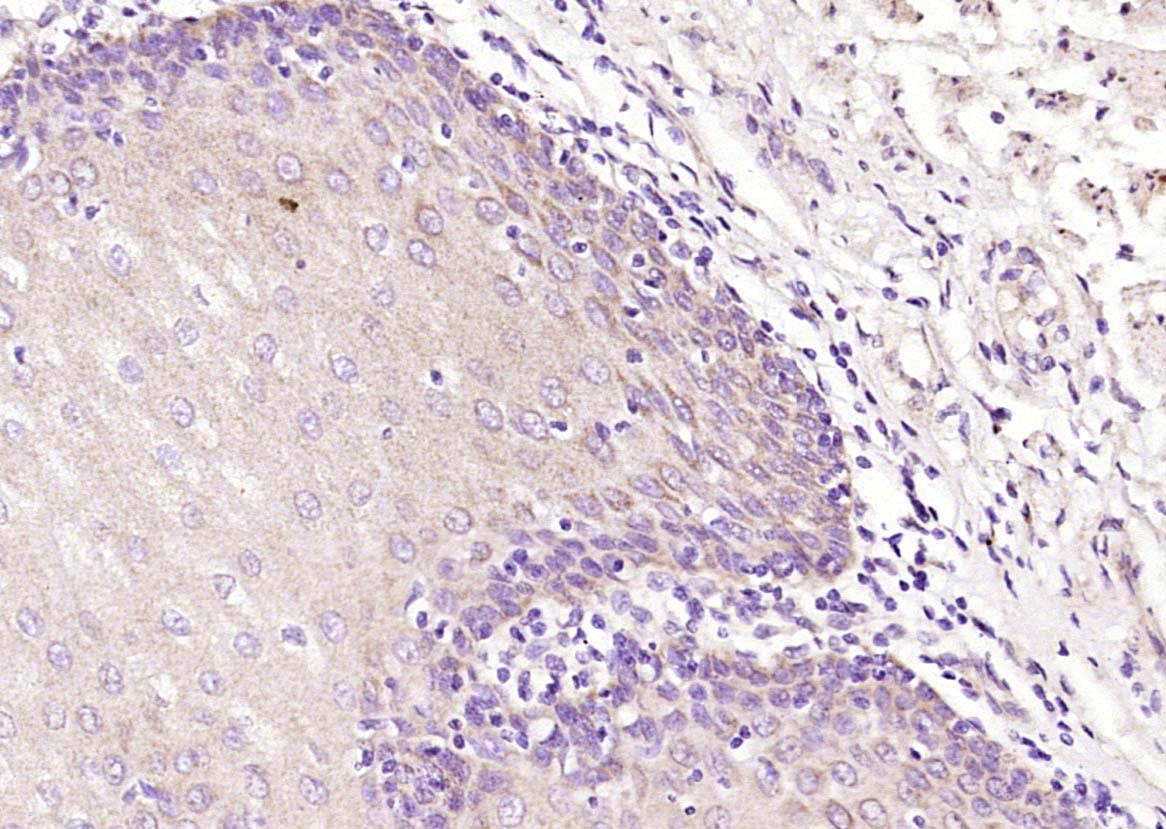

Paraformaldehyde-fixed, paraffin embedded (Human esophageal cancer); Antigen retrieval by boiling in sodium citrate buffer (pH6.0) for 15min; Block endogenous peroxidase by 3% hydrogen peroxide for 20 minutes; Blocking buffer (normal goat serum) at 37°C for 30min; Antibody incubation with (SPINK7) Polyclonal Antibody, Unconjugated (bs-0500R) at 1:400 overnight at 4°C, followed by operating according to SP Kit(Rabbit) (sp-0023) instructionsand DAB staining.

Paraformaldehyde-fixed, paraffin embedded (Human esophageal); Antigen retrieval by boiling in sodium citrate buffer (pH6.0) for 15min; Block endogenous peroxidase by 3% hydrogen peroxide for 20 minutes; Blocking buffer (normal goat serum) at 37°C for 30min; Antibody incubation with (SPINK7) Polyclonal Antibody, Unconjugated (bs-0500R) at 1:400 overnight at 4°C, followed by operating according to SP Kit(Rabbit) (sp-0023) instructionsand DAB staining.